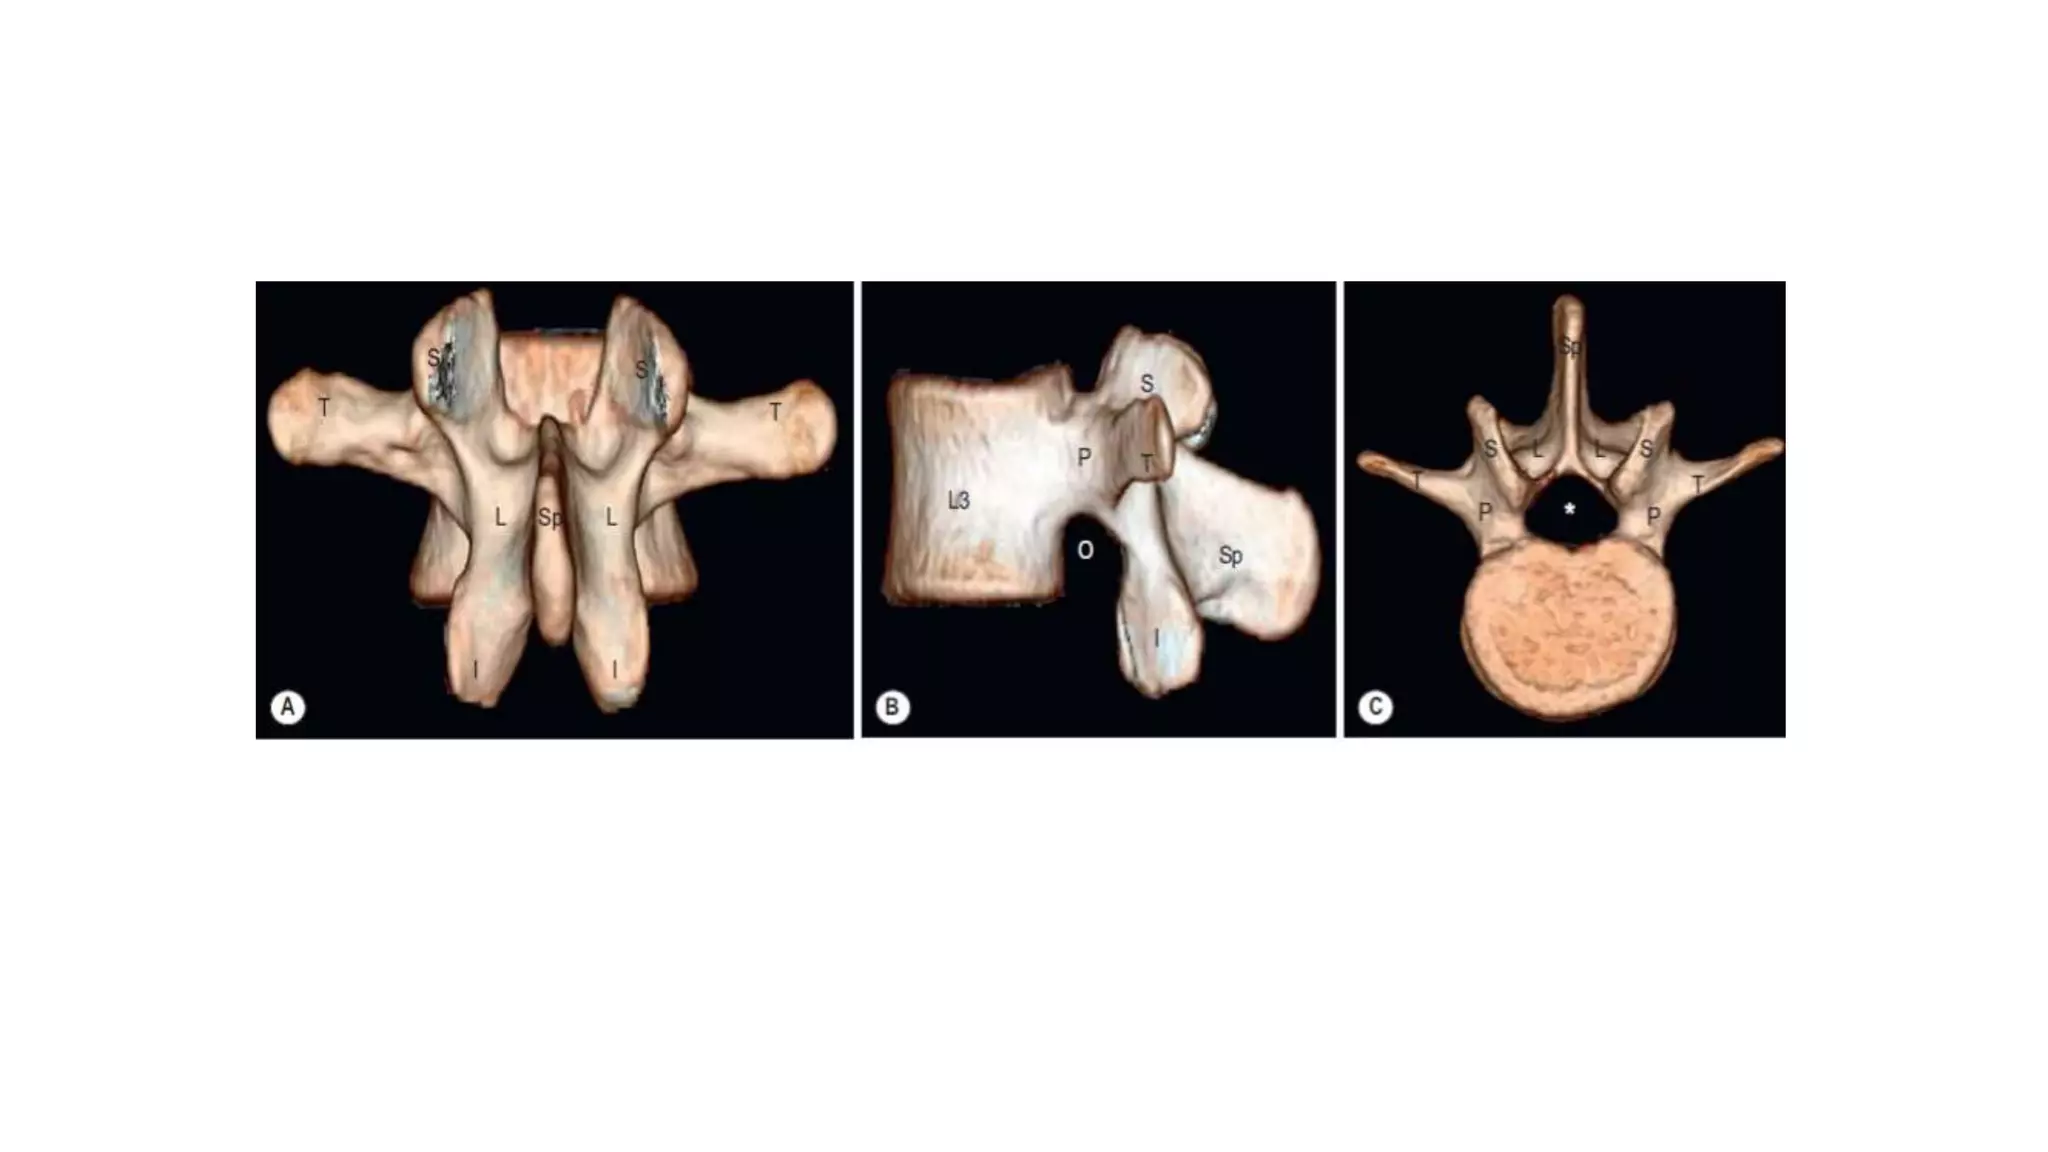

• A typical vertebra

consists of a vertebral

body and a vertebral

arch.

• The vertebral body is

anterior in position and

is the major

weightbearing

component of the bone.

• It increases in size from

vertebra CI to vertebra

LV.

• A typicalvertebra consists of a vertebral body and a vertebral arch. • The vertebral body is anterior in position and is the major weightbearing component of the bone. • It increases in size from vertebra CI to vertebra LV.